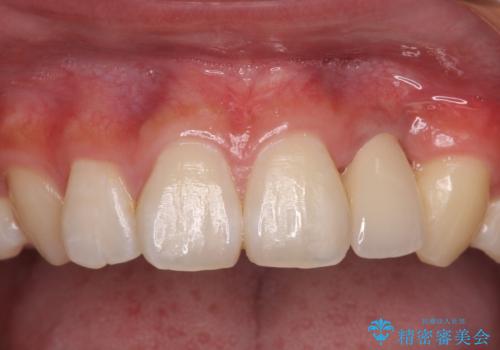

まずは根管治療を行い、症状が落ち着いたことを確認して、オールセラミッククラウンにて補綴治療を行うこととしました。

処置後、下顎の膿の出口はすぐに消えましたが、レントゲン写真からも分かるとおり、歯根途中に穴が開いており、充填材が歯根外にはみ出していました。数ヶ月経過を見たところ、特に異常は認められなかったため、補綴治療を行いました。